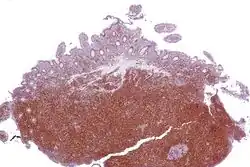

Micrograph of terminal ileum with mantle cell lymphoma (bottom of image - brown colour). Cyclin D1 immunostain.

Micrograph of terminal ileum with mantle cell lymphoma (bottom of image). H&E stain.